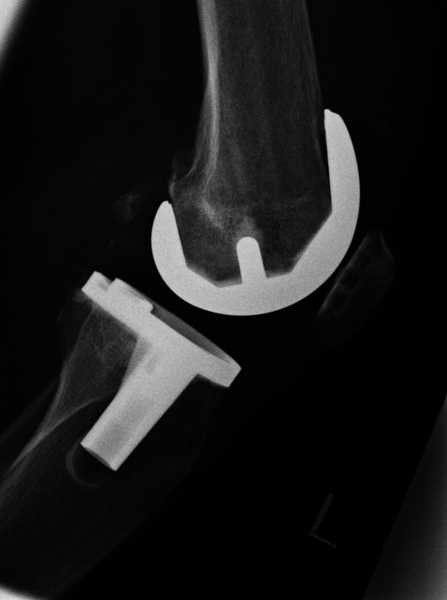

Endoprothetik:

In fortgeschrittenen Fällen, wenn ein großflächiger, schmerzhafter Gelenkverschleiß vorliegt und sämtliche oben genannten Therapieoptionen nicht mehr sinnvoll sind, dann ist - bei entsprechenden Beschwerden - die Therapie der Wahl der Gelenkersatz. Hierbei wird das verschlissene Gelenkareal durch eine künstliche Metalloberfläche ersetzt und zwischen diese Metallpaarung wird als Puffer und zur Verbesserung des Reibungsverhaltens eine Kunsstoffplatte (Polyethylen) eingebracht.